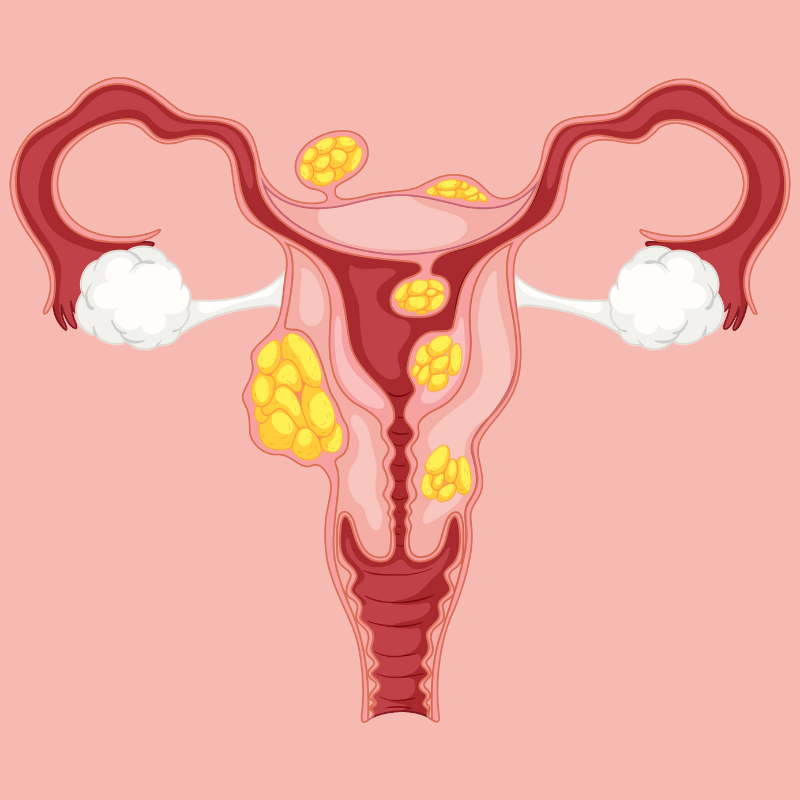

PCOS

Fibroids

Endometriosis

Adenomyosis

Ovarian Cyst